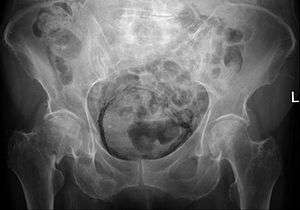

| Regulation of urine production by ADH and aldosterone | |